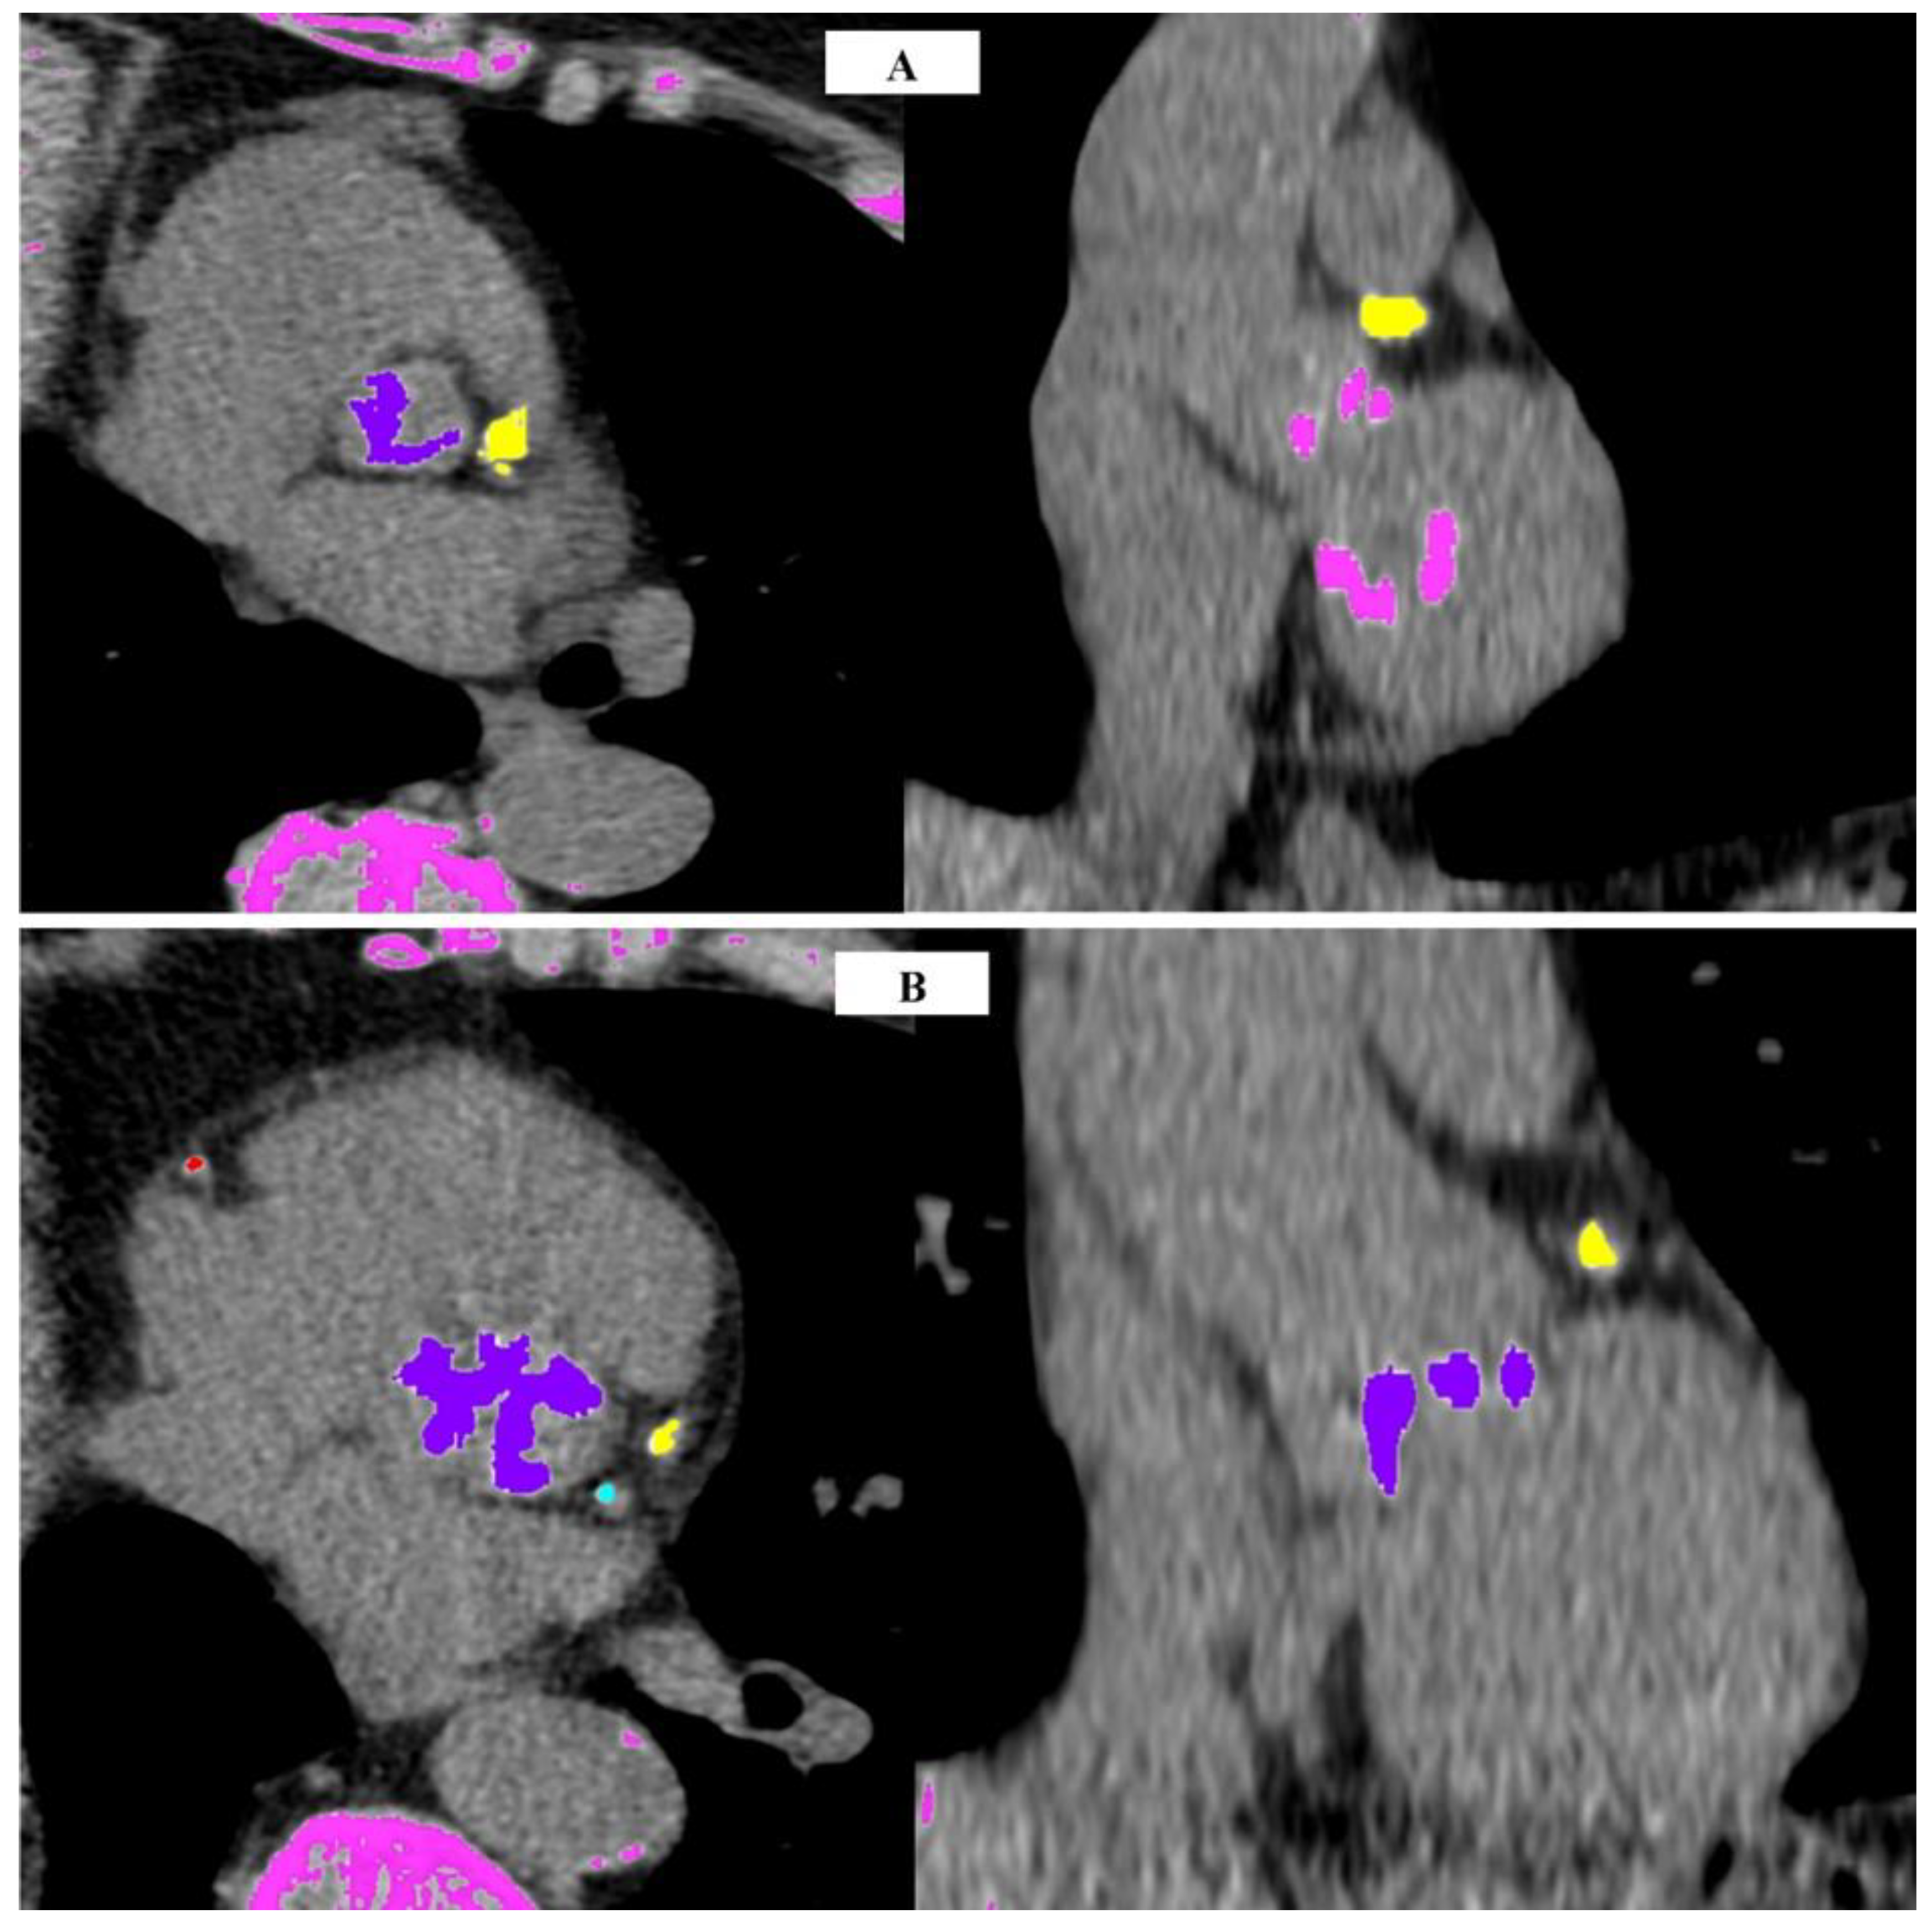

- Abdelkhalek, M.; Daeian, M.; Keshavarz-Motamed, Z. Regional assessment of aortic valve calcification using topographic maps in contrast-enhanced CT: In-vivo sex and severity-based differences in calcific presentation. Quant. Imaging Med. Surg. 2024, 14, 1–19. [Google Scholar] [CrossRef]